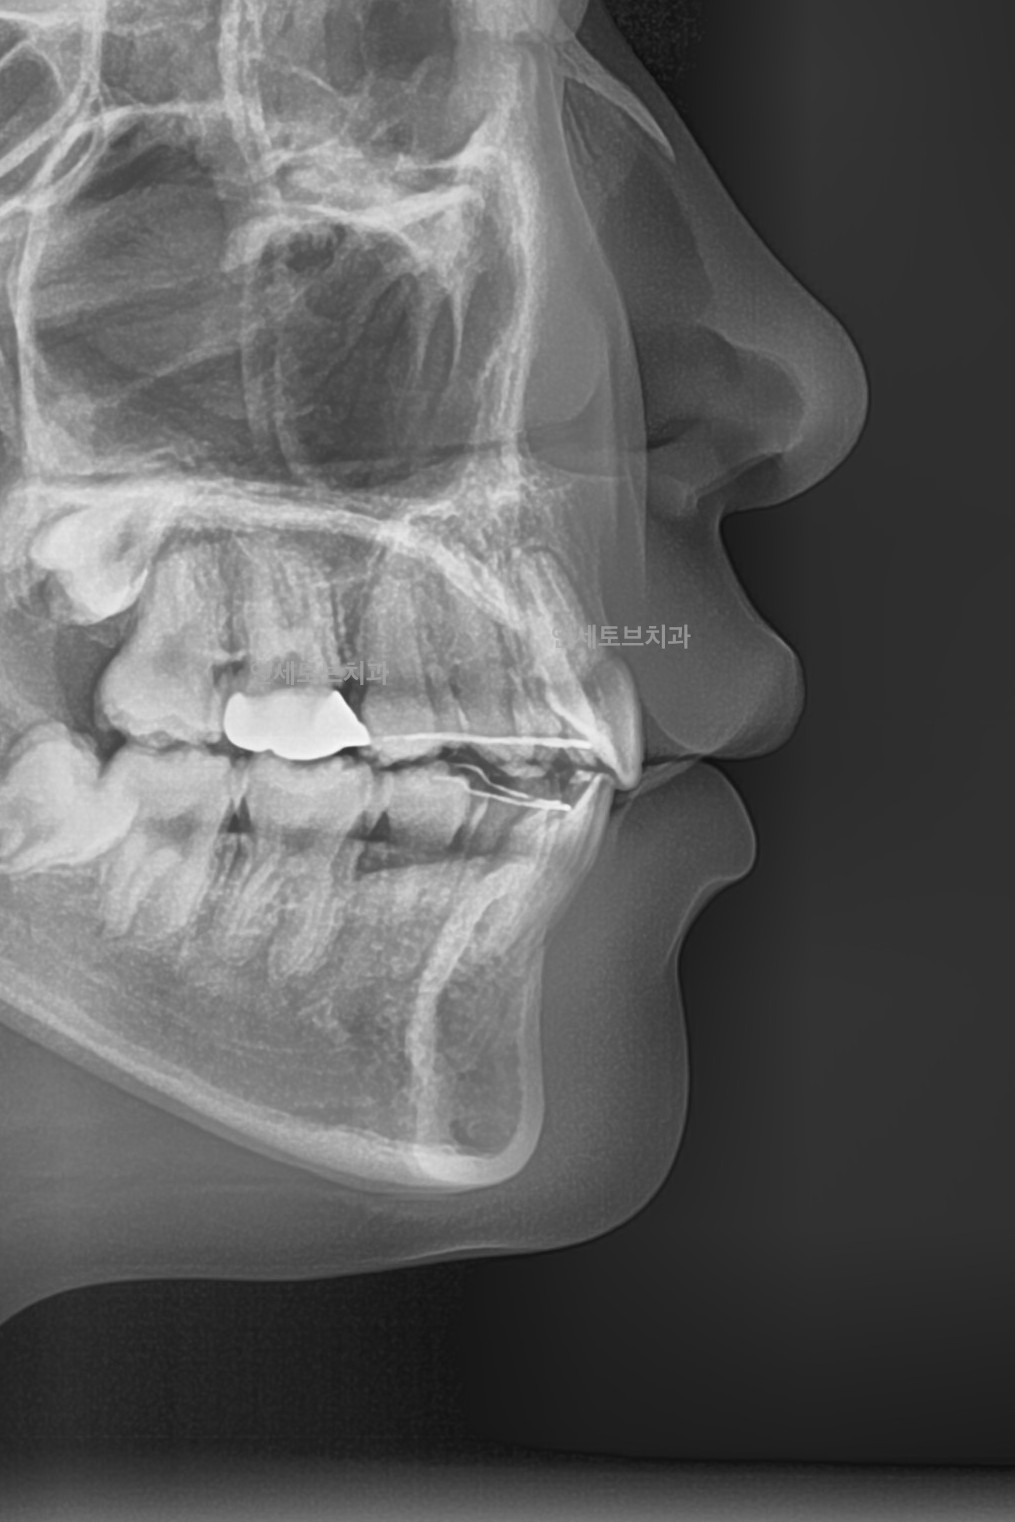

Before

돌출입은 윗니나 아랫니(또는 둘 다)가 정상적인 위치보다 앞으로 튀어나온 상태를 말합니다.

이로 인해 입술이 앞으로 돌출되어 보이고, 측면 얼굴 프로필에서 특히 두드러지게 나타납니다.

한국인을 포함한 동양인에게 비교적 흔하게 나타나는 부정교합 유형입니다.